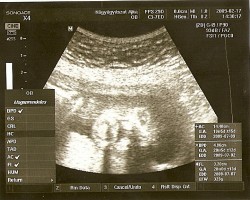

Voltam ma dokinál,és sikerült egy közelit elcsípni az arcáról! :lol: :lol:

Minden okés is!!! Kép

Nagggggyyyyyonnnn ritka az ilyen jó kép hagyományos ultrahanggal! :shock: :shock: :shock: :D :D :D :D :D :D

Még a doki is tök megörült h ilyen képet ritkán tud csinálni! :lol:

Olyan széééép!

Jok az uh kepek,de Timi basszus nagyon kiveheto kislanykad arcvonasa :shock: :shock: :shock: !Csodaszep!!!